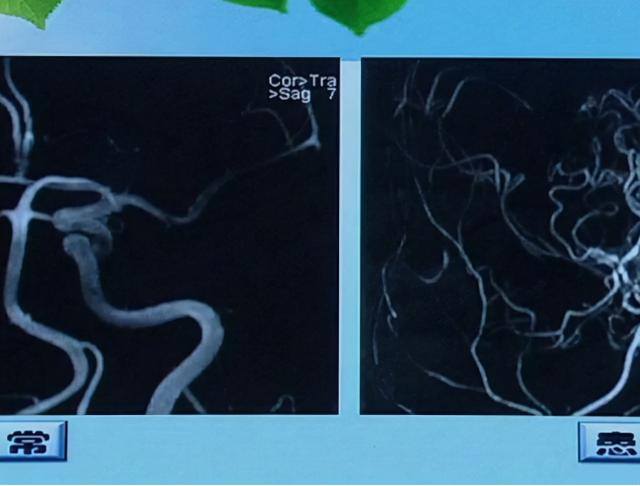

1. 短暂性脑缺血发作。由于脑局部供血出现不足导致相关神经功能缺失。发病时会伴有偏瘫,一过性黑蒙失语以及出现眩晕,走路失调等症状。少数的患者还会有吞咽困难,意识丧失的情况发生,以上症状持续时间一般不超过一天,且可以反复发作,应选择CT检查脑部。

2. 脑梗死。由于动脉粥样硬化,导致血管发生堵塞,脑供血状况异常,从而引起了脑梗死。脑梗死的患者会有身体感觉异常,共济失调,头晕头疼以及眩晕等。随着病情的进一步加剧,则会大大影响到患者生命安全。因此,个人必须要加强防范意识,多注意身体变化。